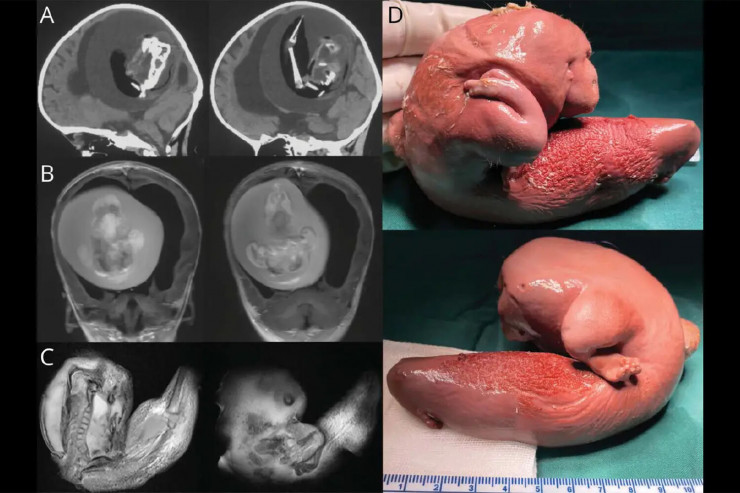

Хирурги из Китая удалили из мозга годовалой девочки плод ее близнеца, передает Tengrinews.kz со ссылкой на gazeta.ru.

Плод длиной около 10 сантиметров обнаружили в мозге девочки, когда родители отвезли ее в больницу из-за увеличения черепа и проблем с моторикой.

Врачи отметили, что у плода развились верхние конечности, кости и даже ногти. Это означает, что он, вероятно, продолжал расти в течение нескольких месяцев в теле сестры. Это было возможно, так как кровеносная система плода была соединена с системой кровообращения девочки.

Фото: Wolters Kluwer Health, Inc.

"Плод в плоде" - это медицинский термин, обозначающий редкое явление, при котором близнецы сливаются в утробе матери и один из них физически развивается внутри другого. Задокументировано всего около 200 случаев "плода в плоде". Их находили в области таза, рта, кишечника и даже мошонки. Случаев, связанных с черепом, насчитывается всего 18. Обычно их находили у младенцев, но несколько случаев были зарегистрированы среди взрослых. После операции по удалению больные обычно полностью выздоравливают.